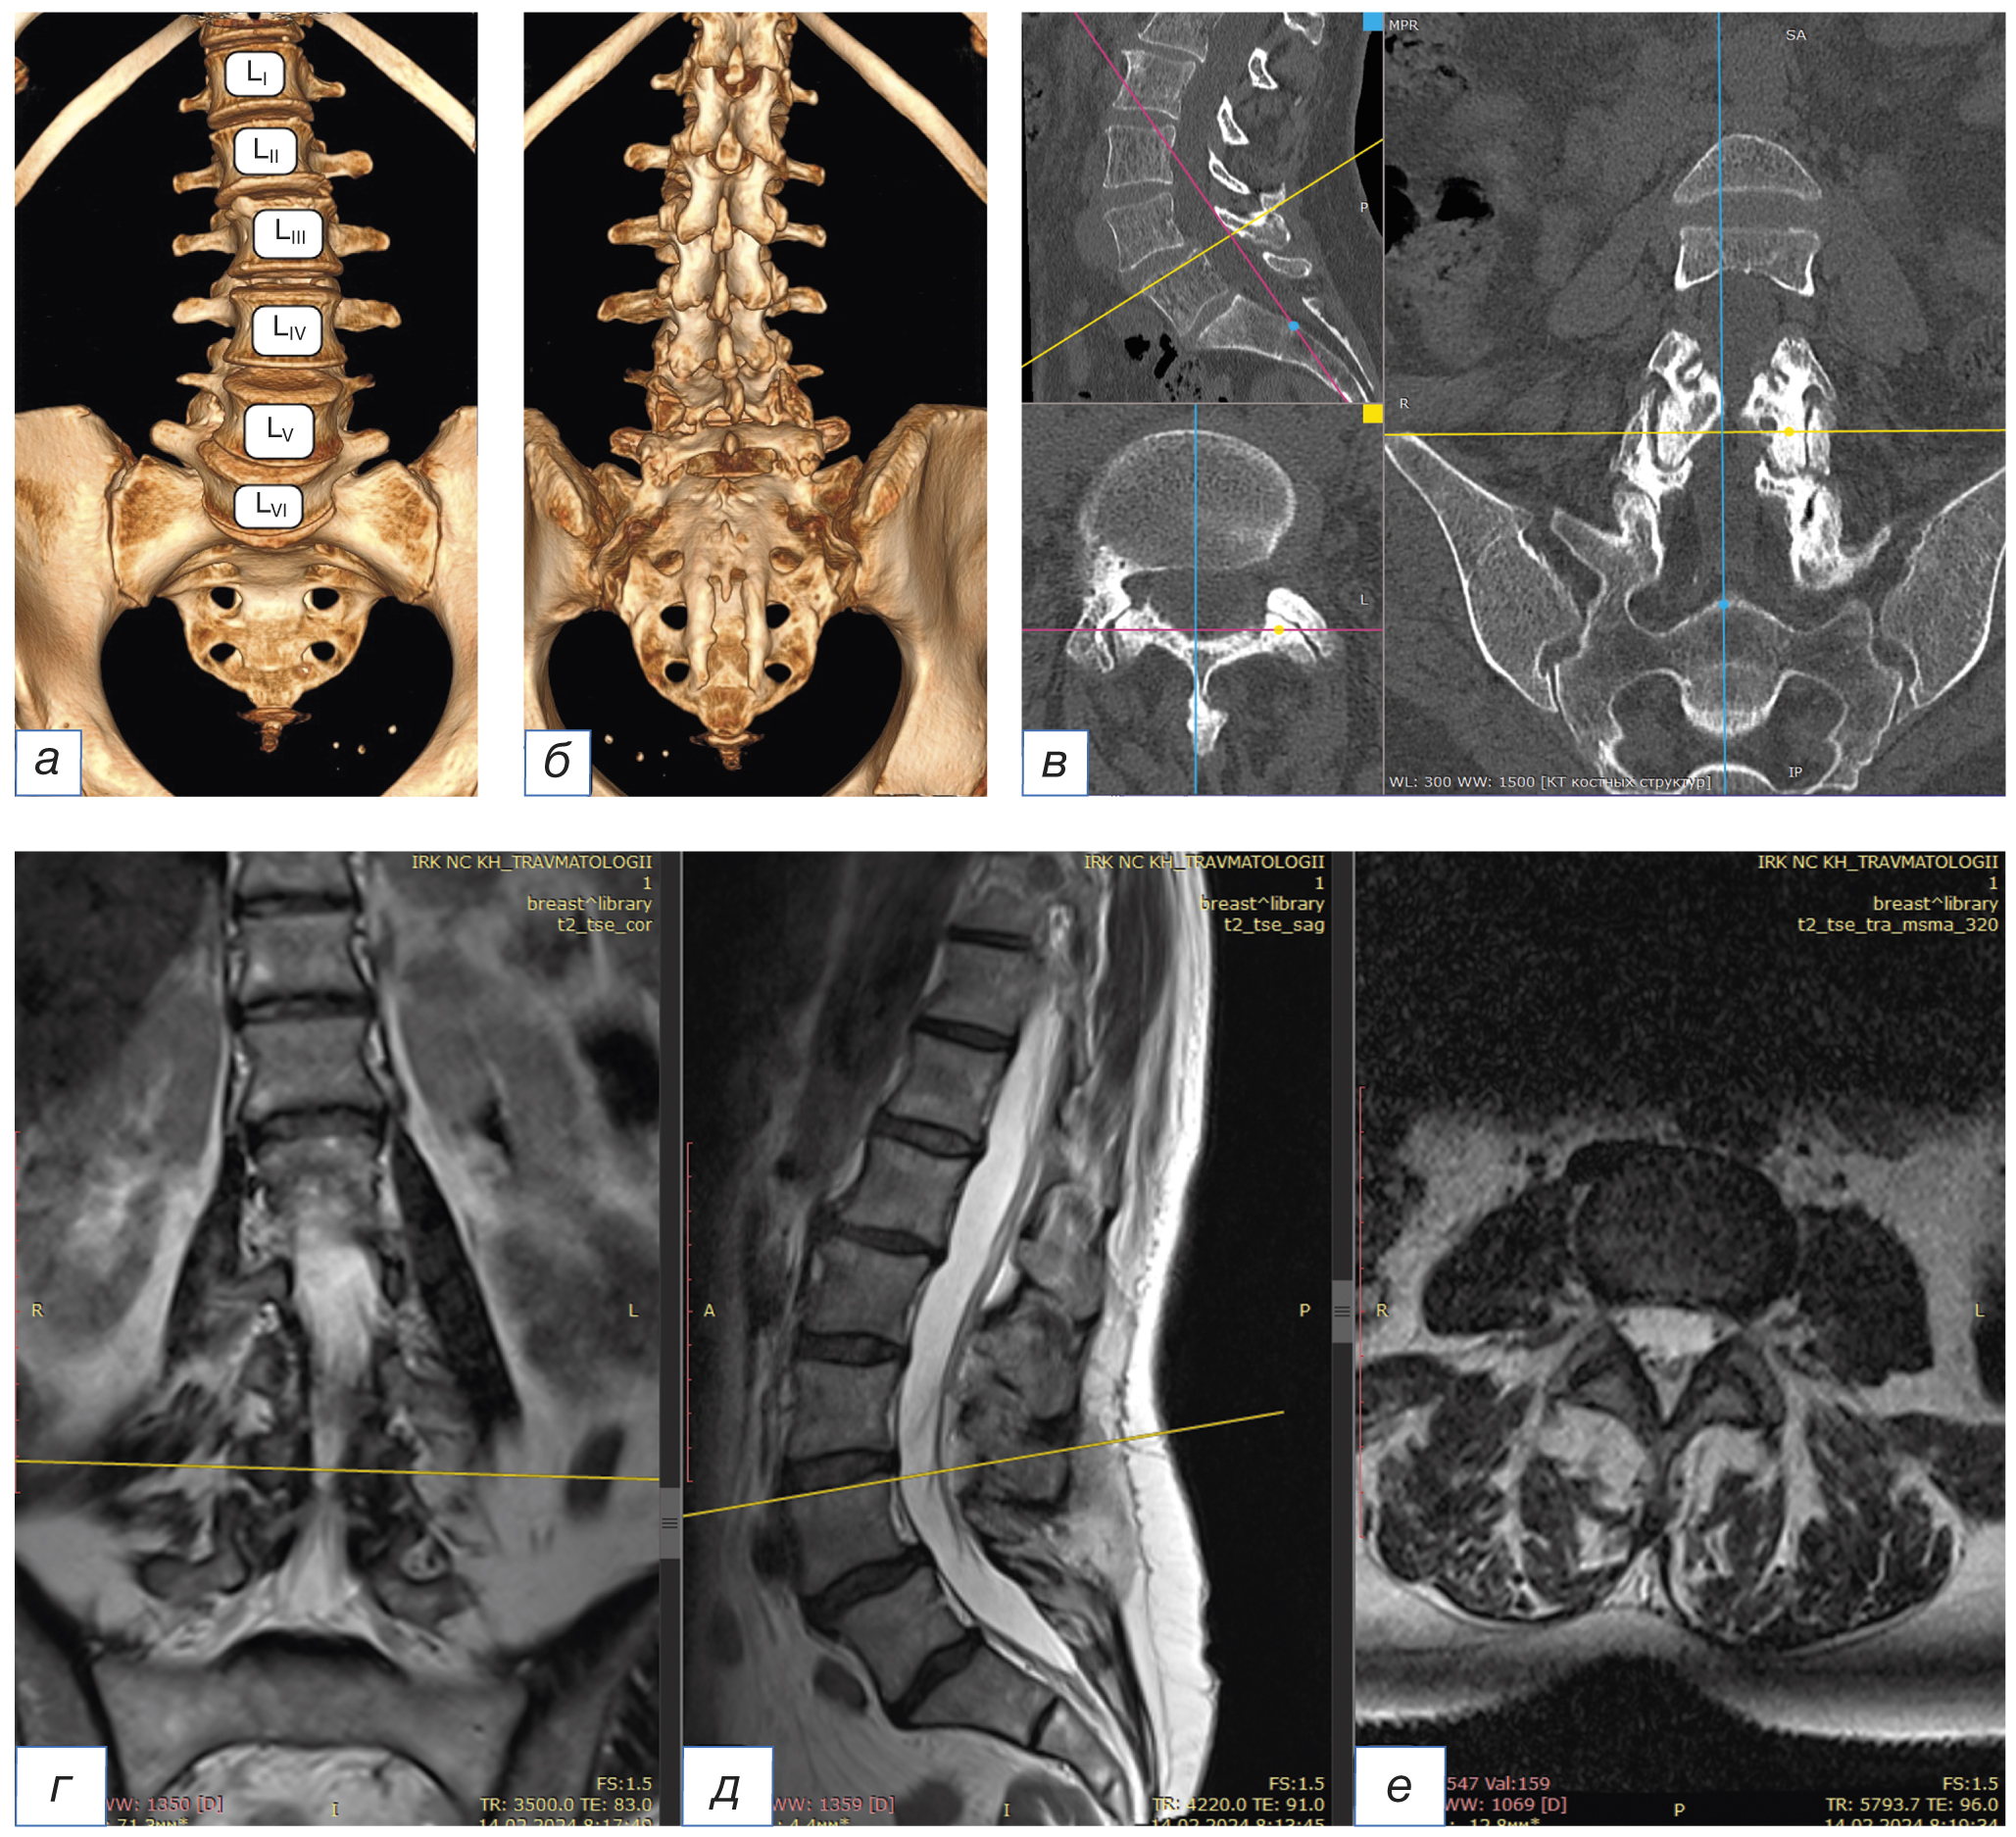

Современные методы интроскопической диагностики, такие как мультиспиральная компьютераная томография, магнитно-резонансная томография, являются основными для выявления дисплазии поясничного отдела позвоночника. В то же время нельзя недооценивать роль рутинной рентгенографии. Такие аномалии развития, как сакрализация или люмбализация LV-позвонка, могут выявляться случайно при проведении нейровизуализационных исследований (мультиспиральная компьютераная томография, магнитно-резонансная томография) и не всегда сопровождаются болевым синдромом или развитием неврологической симптоматики (рис. 4) [15, 17]. Усугубление клинической симптоматики у пациентов связано, как правило, с прогредиентным течением дегенеративной патологии позвоночника, сопутствующим сколиозом, спондилолизным спондилолистезом, грыжей межпозвонкового диска, незаращением части дуг позвонков (spina bifida occulta) [18–20].

Рис. 4. Люмбализация по результатам мультиспиральной компьютерной томографии: 3D-МСКТ, передняя проекция (а), 3D-МСКТ, задняя проекция (б), МСКТ-реконструкция с полипроекционным сканом на уровне LV–LVI (в). Показано шесть поясничных позвонков. Левосторонний сколиоз с искривлением позвоночника до 170°, с вершиной дуги на LIV. Гиперлордоз. Тело позвонка LV смещено вентрально на 0,46 см (антеспондилолистез I степени). Спондилоартроз LIV–LV, LV–LVI, III степень по D. Weishaupt [14]. Люмбализация по результатам магнитно-резонансной томографии, Т2-взвешенное изображение: фронтальная (г), сагиттальная (д) и аксиальная (е) проекции с гиперинтенсивным сигналом в дугоотростчатых суставах LIV–LV, LV–LVI, III степень по A. Fujiwara [14]

Fig. 4. Lumbarization from a multispiral computer tomography scan: MSCT 3D front projection (а), MSCT 3D rear projection (б), and MSCT reconstruction with a projection scan at the LV–LVI level (в). Six lumbar vertebrae are shown. Left-sided scoliosis with curvature of the spine up to 170° with the apex of the arch on LIV. Hyperlordosis. The body of the LV vertebra is displaced ventrally by 0.46 cm (grade 1 antespondylolisthesis). Spondyloarthrosis LIV–LV, LV–LVI III degree according to D. Weishaupt [14]. Lumbarization from a magnetic resonance imaging, T2-weighted image: frontal projection (г), sagittal projection (д), and axial projection (е) with hyperintensive signal in arched joints LIV–LV, LV–LVI III degree according to A. Fujiwara [14]